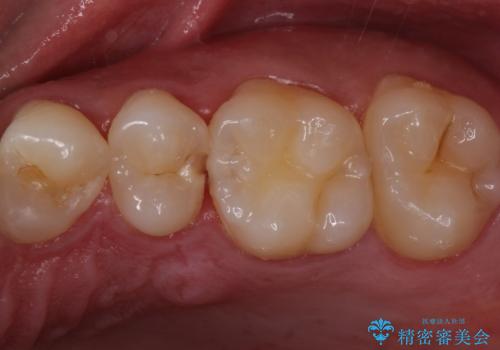

歯と歯の間の虫歯 セラミックインレーでの治療

- 検査の結果虫歯が見つかった患者様です。

レントゲン画像と視診から詰め物で対応可能と判断したためインレーでの修復をしていきます。

- 左上5 セラミックインレー/77,000円費用は治療当時の料金となります

適合の良いインレーは段差がない上にセラミックは汚れがつきにくい材料であるため今後の虫歯発生リスクを抑えることに繋がります。